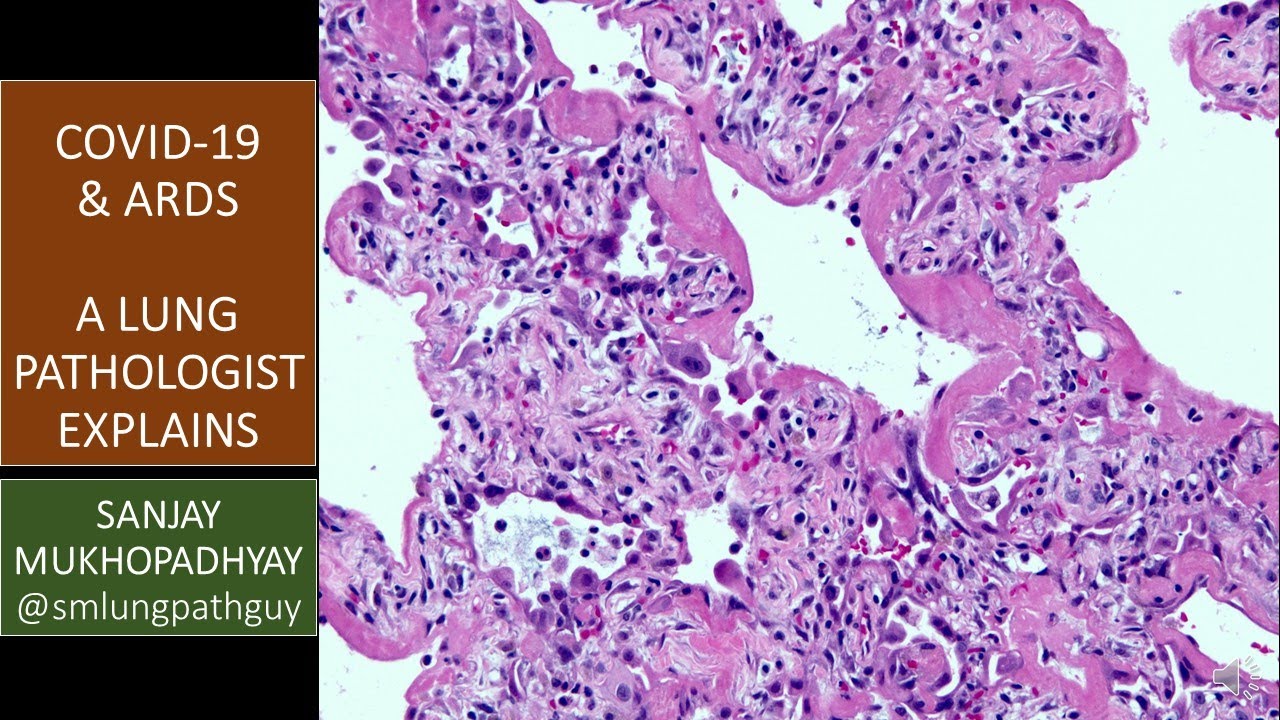

This brief video by an expert in lung pathology explains what pathologists see under the microscope in lung tissue from patients who are severely ill from viral infections such as COVID-19, which is currently causing a pandemic. See links below to 2 recent videos that have left an impression on the creator of this video as far as COVID-19 goes.

I am a medical doctor (a pathologist). My job involves diagnosing diseases such as lung cancer, mesothelioma, infections and interstitial lung disease by examining tissue samples under a microscope. I also teach medical students, pathology residents, and pulmonary and critical care fellows. I am the author of a textbook of non-neoplastic lung pathology published by Cambridge University Press. Check it out here: